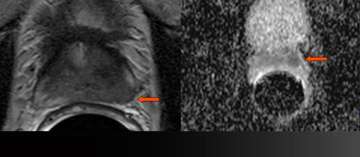

8) Benign Disease (Infertility)

Benign Disease (Infertility)

• Young man presents with infertility (azospermia)

• Workup and medical history otherwise noncontributory

• Muellerian duct remnant in central upper prostate may obstruct ejaculatory ducts

• Left seminal vesicles are atrophic

• Read More >